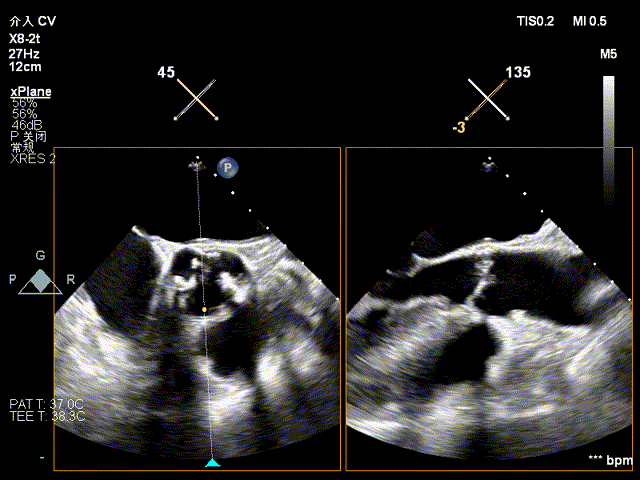

术前食道超声

手术过程

TAVR部分:

经股动脉上行猪尾导管,主动脉根部造影

主动脉根部造影

显露心尖,于心尖预置双层3-0Prolene带垫片荷包,穿刺心尖,进入造影导丝及鞘管,经导丝将单弯导管送至降主动脉,交换支撑导丝至降主动脉。

沿超硬导丝送入预装好的26mm SAPIEN 3瓣膜,经心尖进入左心室,跨过主动脉瓣置于主动脉瓣上

瓣膜定位

瓣膜定位后,心脏起搏至180bpm,血压下降后,在主动脉根部造影的同时迅速充盈球囊,释放瓣膜

瓣膜释放

复查造影示瓣膜位置,功能,形态良好,无冠脉堵塞,术中TEE证实主动脉瓣生物瓣位置及功能正常,未见瓣周漏,仅微量反流。